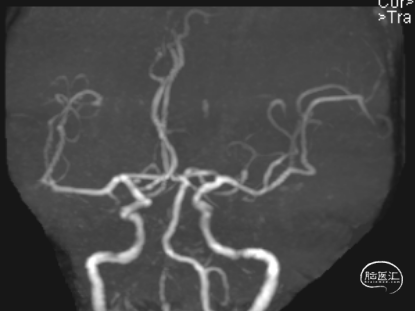

头颈CTA:左侧椎动脉起始、左侧锁骨下动脉重度狭窄。

LSub

LV1